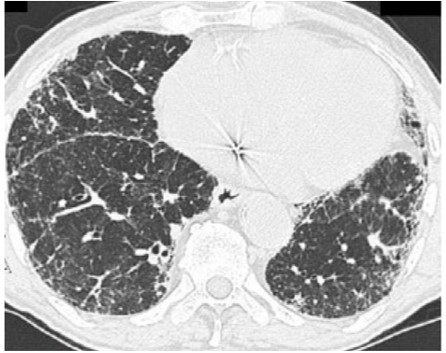

Example

When characteristics suggestive of fibrosis are visible on HRCT scans but do not meet the criteria of UIP or probable UIP, the images should be classified as indeterminate for UIP.5 UIP pattern may be found on histological testing of patients with HRCT patterns indeterminate for UIP.3,6

Image courtesy of and used with permission from Robert Suh, MD.